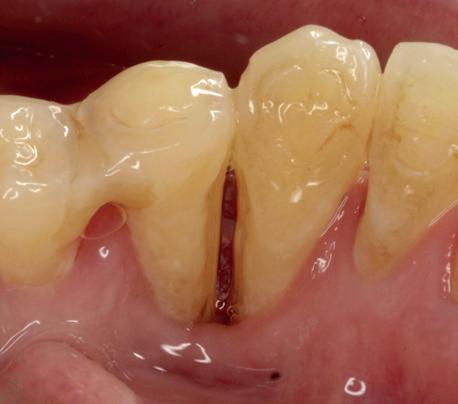

Uit het röntgenonderzoek blijkt dat op de locatie van de 22 veel bot verloren is gegaan en dat er niet direct een implantaat geplaatst kan worden. Om die reden is een botaugmentatie geïndiceerd. Wel zijn distaal van de 21 en mesiaal van de 23 de botpieken aanwezig die de papillen ondersteunen. Naast te weinig bot, is op de locatie 22 in bucco-linguale richting ook te weinig volume gingiva aanwezig. Daarom zal er tevens een soft tissue graft aangebracht worden. Tijdens deze behandeling wordt ook de recessie op de 23 zoveel mogelijk bedekt (foto 7 en 8).

Tijdens het verwijderen van het membraan is het botvolume klinisch waarneembaar en blijkt dat er voldoende bot is om het implantaat te kunnen plaat-

sen. Tijdens deze procedure wordt er ook een free gingival graft van het palatum gehaald. Deze wordt buccaal aangebracht van de 22 en 23 om zo de recessie zoveel mogelijk te bedekken en de papil tussen de 22 en 23 van meer volume te voorzien.

De flap en graft worden met poly-propelene 6.0 hechtingen gefixeerd. De tijdelijke reconstructie wordt herplaatst (foto 17-20).